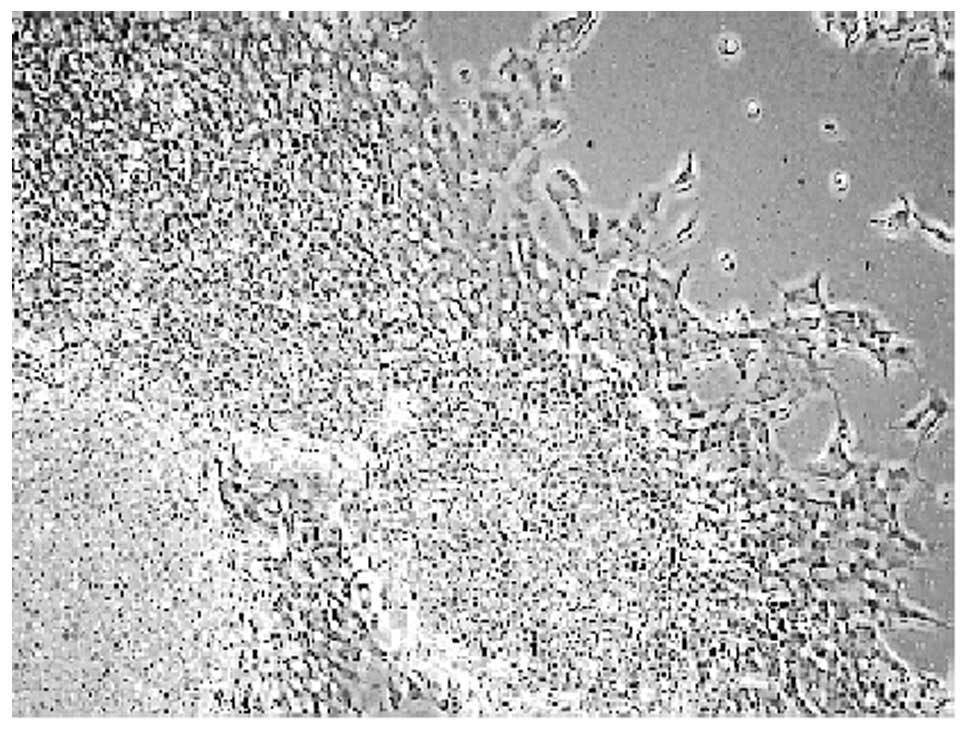

Morphological differentiation of SH-SY5Y cells

It was observed that the undifferentiated neuroblastoma cells grew mostly together in the form of clumps (Fig. 1A). On the other hand, cells treated with all-trans-retinoic acid (RA) for 72 h resulted in a significant cellular differentiation, characterized with elongated neurites (Fig. 1B). The concentration of RA was based on previous studies (10). Our results clearly demonstrate that RA promotes SH-SY5Y cell differentiation.

Figure 1

Morphology of undifferentiated and differentiated human SH-SY5Y cells. Cells were grown in culture dishes in the complete medium without RA (A) or with 10 μM RA (B). Unstained cells were photographed after 72 h of RA treatment using an inverted phase contrast IX-70 Olympus microscope. Neurite extensions in RA-induced differentiation (B) were seen clearly.

The morphological features of differentiated cells clearly showed that the cells have elongated neurite extensions (Fig. 1), which are in agreement with previous reports (18,19). We next studied the effect of morphine on MOR-1 mRNA levels in the differentiated cells. It was found that morphine downregulated the MOR-1 levels significantly (Fig. 4). The downregulation of MOR-1 with morphine treatment was also observed earlier in different cell lines (20–22).